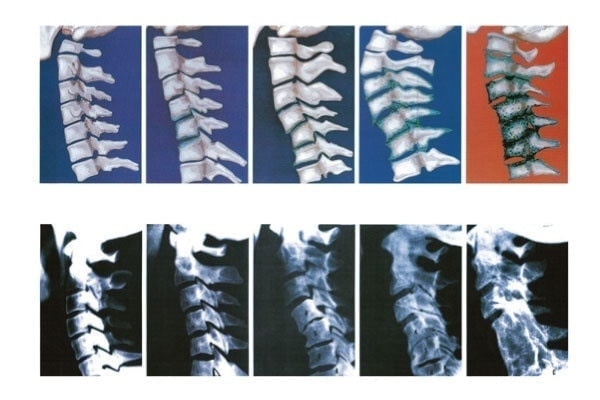

頚椎症は首の骨(頚椎)の中を通る神経が圧迫されることで生じるもので、肩や首の痛み、手や足にしびれやだるさなどの悪影響があります。

脊柱管や椎間孔に狭窄が起こりますから、一度発症すると一筋縄ではいかなくなります。

また、脊髄にまで悪影響を及ぼす頚椎症性脊髄症は椎間板が原因で、骨に棘状の骨棘が生じ、靭帯が厚く硬くなって脊髄の圧迫に至ります。

一方、頚椎症性神経根症は頚椎の変性により、椎間孔に狭窄が起こり神経根が圧迫され、やがて痛みを引き起こします。

このように、脊髄が圧迫されるか神経根が圧迫されるかによって、頚椎症でも病名や症状は違ってきます。